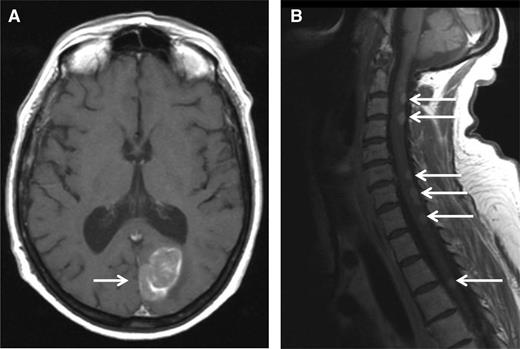

A 51-year-old woman was diagnosed with IgA-κ MM in 2004. At this time, she presented with symptomatic myeloma-related bone lesions, and a bone marrow aspirate confirmed the presence of 33% PCs. The International Scoring System (ISS) score was low (I), and a fluorescence in situ hybridization (FISH) analysis did not reveal any adverse cytogenetic factors (t[4;14] translocation, 17p deletion, and t[14;16] translocation). The first line of therapy consisted of 4 cycles of vincristine-adriamycin-dexamethasone followed by high-dose melphalan/ASCT. The patient achieved a complete remission (CR) after the completion of therapy, but the disease relapsed only 6 months after transplantation. At this time, the patient was treated with a regimen consisting of bortezomib-thalidomide-dexamethasone. During the fifth cycle of bortezomib-thalidomide-dexamethasone, she developed progressive ataxia, and an MRI scan revealed a paramedian occipital lesion (3.6 × 2 cm), as well as multiple posterior lesions of the medulla from C2 to T6 (Figure 1). A CSF analysis revealed the presence of 30 leukocytes per mm3, 80% of which were clonal PCs. At the same time, the percentage of bone marrow PCs was <5%, and no M-component was present in serum or urine. Therefore, we arrived at the diagnosis of a relapsed CNS EMM. The patient then started lenalidomide (25 mg/d, days 1-21) plus high-dose dexamethasone (40 mg/d, days 1-4; days 15-18) (Len-Dex) therapy in combination with cranial irradiation (30 grays) plus intrathecal (IT) injections of methotrexate (15 mg), cytarabine (40 mg), and hydrocortisone (20 mg) until the disappearance of PCs from the CSF (5 IT injections total). The clinical evolution was favorable with the disappearance of neurologic symptoms and the disappearance of both MRI lesions and CSF abnormalities. The patient continued to receive Len-Dex therapy, but the disease recurred after cycle 12 with the same CNS involvement. At that point, treatment was discontinued, and the patient died 3 weeks later.

MRI. MRI (T1 weighted) showing an occipital mass with leptomeningeal involvement (A, white arrow) and multiple posterior medullary lesions (B, white arrows), in a relapsed MM patient who developed progressive ataxia.